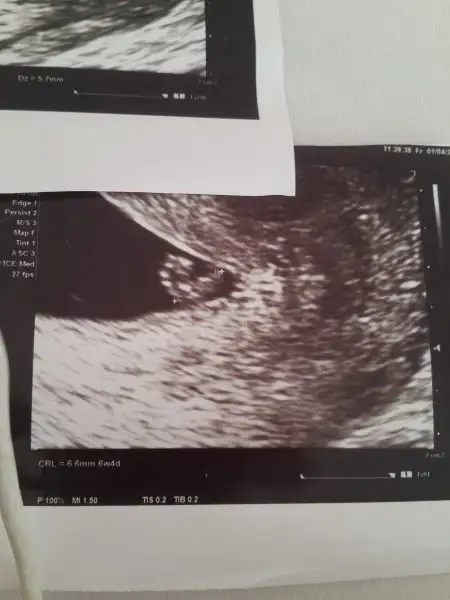

Eki Görüntüle 1810649 Buda benim 7+1 haftalik alttan échographieh ile cekilmis sekli bana da yorum yapar misinizHavalianne__

Teoriye göre erkek oluyorKızlar meraba rabbim bebeklerimizi korusun inş bizlere bağışlasın ... bende baktım da anlayamadım vajinal de tam tersi mi oluyor . Yani vajinal ultrasonda sağda duruyor benim bebeğim erkek mi oluyor kız mı

ramzi teorisine gore cinsiyet belirleme googlden arat canim sanirim buraya gelen yok birde oraya usg paylas :)3 yilık kadinlar kulübü takipçisi olarak yeni üye oldum :) Arkadaşlar banada bir tahminde bulunabilirmisiniz sat göre 6+1 gebeliğin oluştuğu güne görede 4+1 vajinal ugs :)

Canım 6+4 bebişin ultrason kagıdında yazıyor 6+1 değil. Benimkinin tam tersi duruyor bana kız demişti burdan bi arkadas seninki erkek oluyor ona göre :)3 yilık kadinlar kulübü takipçisi olarak yeni üye oldum :) Arkadaşlar banada bir tahminde bulunabilirmisiniz sat göre 6+1 gebeliğin oluştuğu güne görede 4+1 vajinal ugs :)